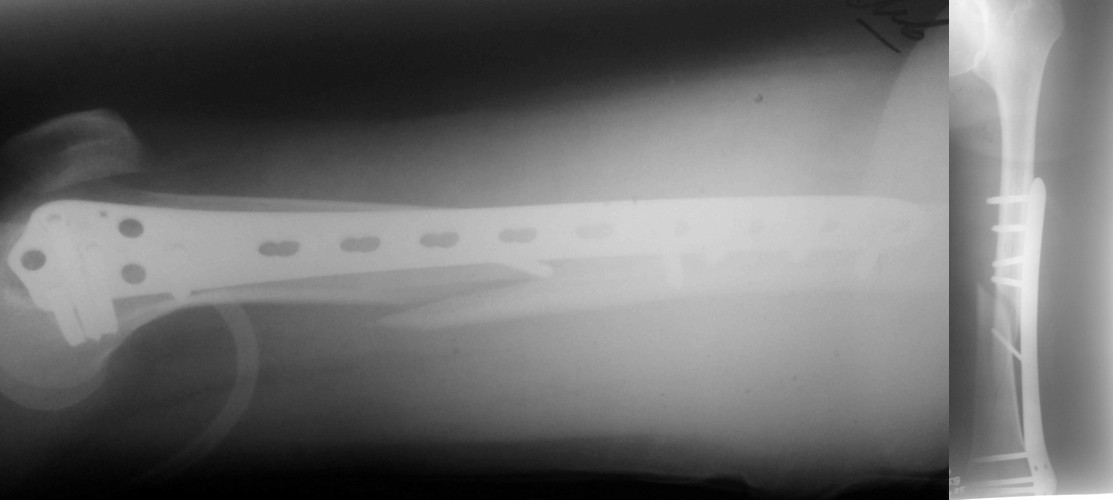

Уважаемые коллеги! 5.08.11 синтез бедренной кости пластиной LCP для дистального бедра.

Прошу совета. П-ка, 59 лет, автодорожная травма, перелом винтообразный н/3 левой бедренной кости. Планировалась закрытая репозиция и малоинвазивный доступ. по ходу операции пришлось немного открыть зону перелома для репозиции. Под контролем ЭОП вроде на столе смещение небольшое было и по оси терпимо. Сделали рентген контроль и получили вот картину. Еще обломилась головка кортикального винта. Синтез то стабильный. Только смещение не только не устранили, но кажется еще чуть больше стало (не могу) первичный снимок сделать). Склонен к ресинтезу и исправлению смещения из расширенного доступа. Как лучше выполнить репозицию? Какие можно использовать приемы репозиции? Спасибо.